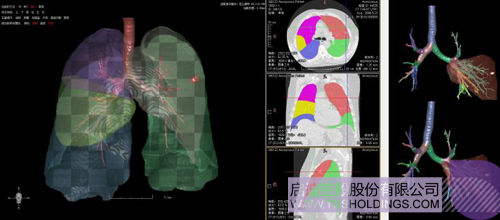

醫療影像智能分析是指運用人工智能技術、計算機視覺技術以及計算幾何技術對醫療影像進行自動分析,幫助醫生定位病癥、分析、跟蹤病情,并通過量化數據輔助醫生做出診斷,目前其旗艦產品“數字肺”已經覆蓋多種肺部疾病的早期檢測、診斷、跟蹤、術前規劃等完整的醫療流程。在臨床實踐中,超過80%的醫療數據來自醫療影像,這些影像數據通常需要專業醫生進行解讀,工作的重復性高、效率偏低。如果能夠運用智能影像分析技術,同時結合臨床表現以及既往病例進行全面分析,那么就可以大幅度提升影像診斷效率和準確性,讓專業醫生的寶貴時間集中在復雜病情的診斷和治療等環節。

數字肺——肺結節手術規劃系統

完整的三維影像智能分析技術;

完整的三維可視化以及相關建模、幾何分析技術;